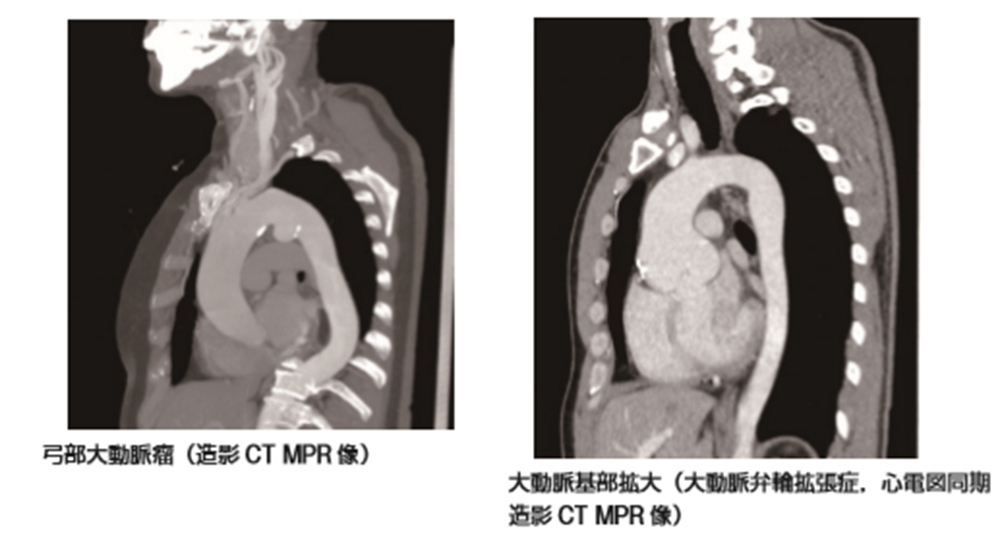

動脈瘤は、動脈の壁が弱くなると発生します。動脈の内側からの圧力が蓄積し、動脈壁の弱い部分が外側に膨らむ可能性があります。この膨らみが動脈瘤です。

腹部大動脈瘤 (AAA) は、血液を心臓から体の残りの部分に移動させる主要な動脈、つまり大動脈の膨らみです。胴体を通って流れ、肝臓や腎臓などの臓器に血液を供給します。

この血管は2つに分かれて足まで伸びます。 AAA は、大動脈が分割される直前の部分で発生します。

AAA をスクリーニングするために、医師は次のような医用画像技術を使用します。

- CT スキャン:このスキャンでは、X 線によって AAA の詳細な画像が作成されます。